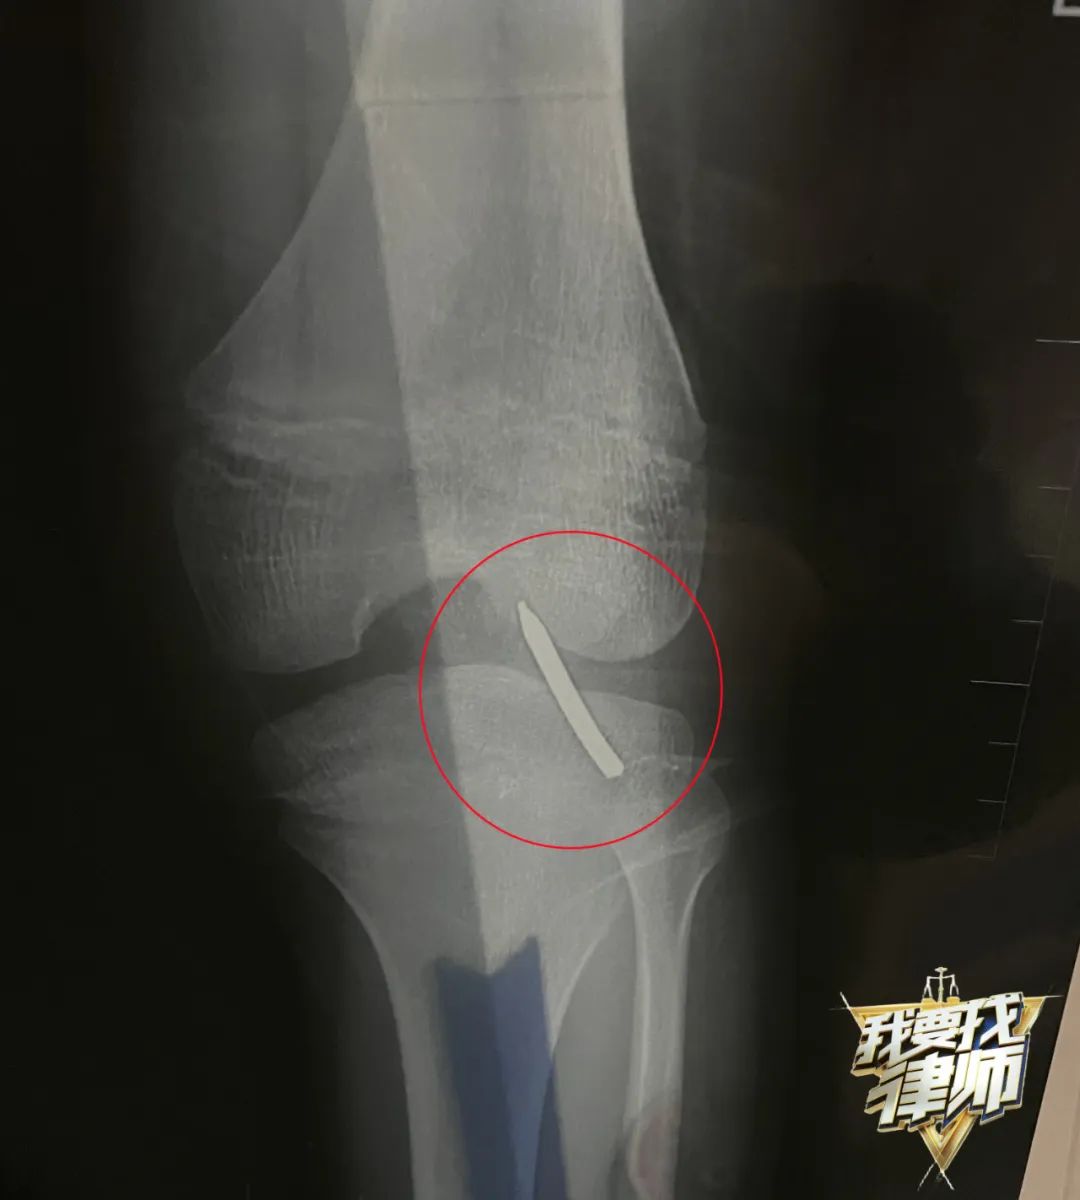

法律咨詢、疑難解答、起訴建議、監(jiān)督執(zhí)行,上我的長沙APP《我要找律師》專區(qū)一鍵通辦。11月25日下午2點(diǎn),家住雨花區(qū)保利城的10歲男童晨晨在小區(qū)一樓打乒乓球,撿球時不慎跌入綠化帶中,爬起來時發(fā)現(xiàn)腿部掛著一塊釘板,銹跡斑斑的鋼釘已經(jīng)插入關(guān)節(jié),晨晨被立即送醫(yī)。

晨晨隨后被送到了長沙市中心醫(yī)院治療,因為鋼釘已經(jīng)插入晨晨膝蓋骨內(nèi)無法取出,直到消防人員用液壓鉗剪斷鋼釘,晨晨才得以進(jìn)入手術(shù)室治療。

目前,晨晨已經(jīng)停課在家中治療,不僅耽誤了學(xué)習(xí),孩子也受了不少罪,這讓晨晨的家人既難受又氣憤!罢掌瑘蟾嫔蠈懙氖卿撫敳迦胂ドw骨8毫米,現(xiàn)在已經(jīng)出院了,但是膝蓋完全彎不了!

圖片鋼釘插入晨晨膝蓋骨內(nèi)